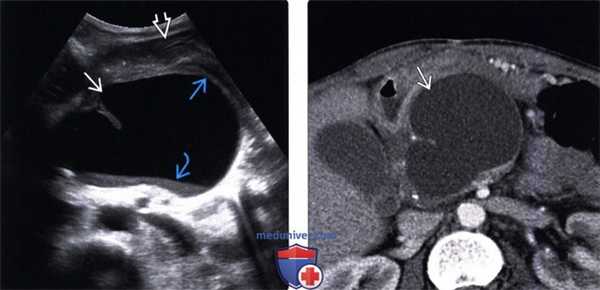

(Левый) Трансабдоминальное УЗИ, поперечное сканирование: анэхогенное образование с четким контуром, эффектом дистального акустического усиления, располагающееся в области хвоста поджелудочной железы, соответствует псевдокисте.

(Правый) Аксиальная КТ с контрастированием у этого же пациента: визуализируется низкоинтенсивное кистозное поражение, с четким контуром и тонкой стенкой, располагающееся в области хвоста поджелудочной железы. Можно отметить отсутствие структур, накапливающих контраст, и выраженную атрофию ткани железы. (Левый) Трансабдоминальное УЗИ, поперечное сканирование в проекции поджелудочной железы: визуализируется однокамерное кистозное образование с четким контуром и эффектом дистального псевдоусиления. Обратите внимание на эхогенное содержимое и некротическое расслоение, что характерно для сложной псевдокисты.